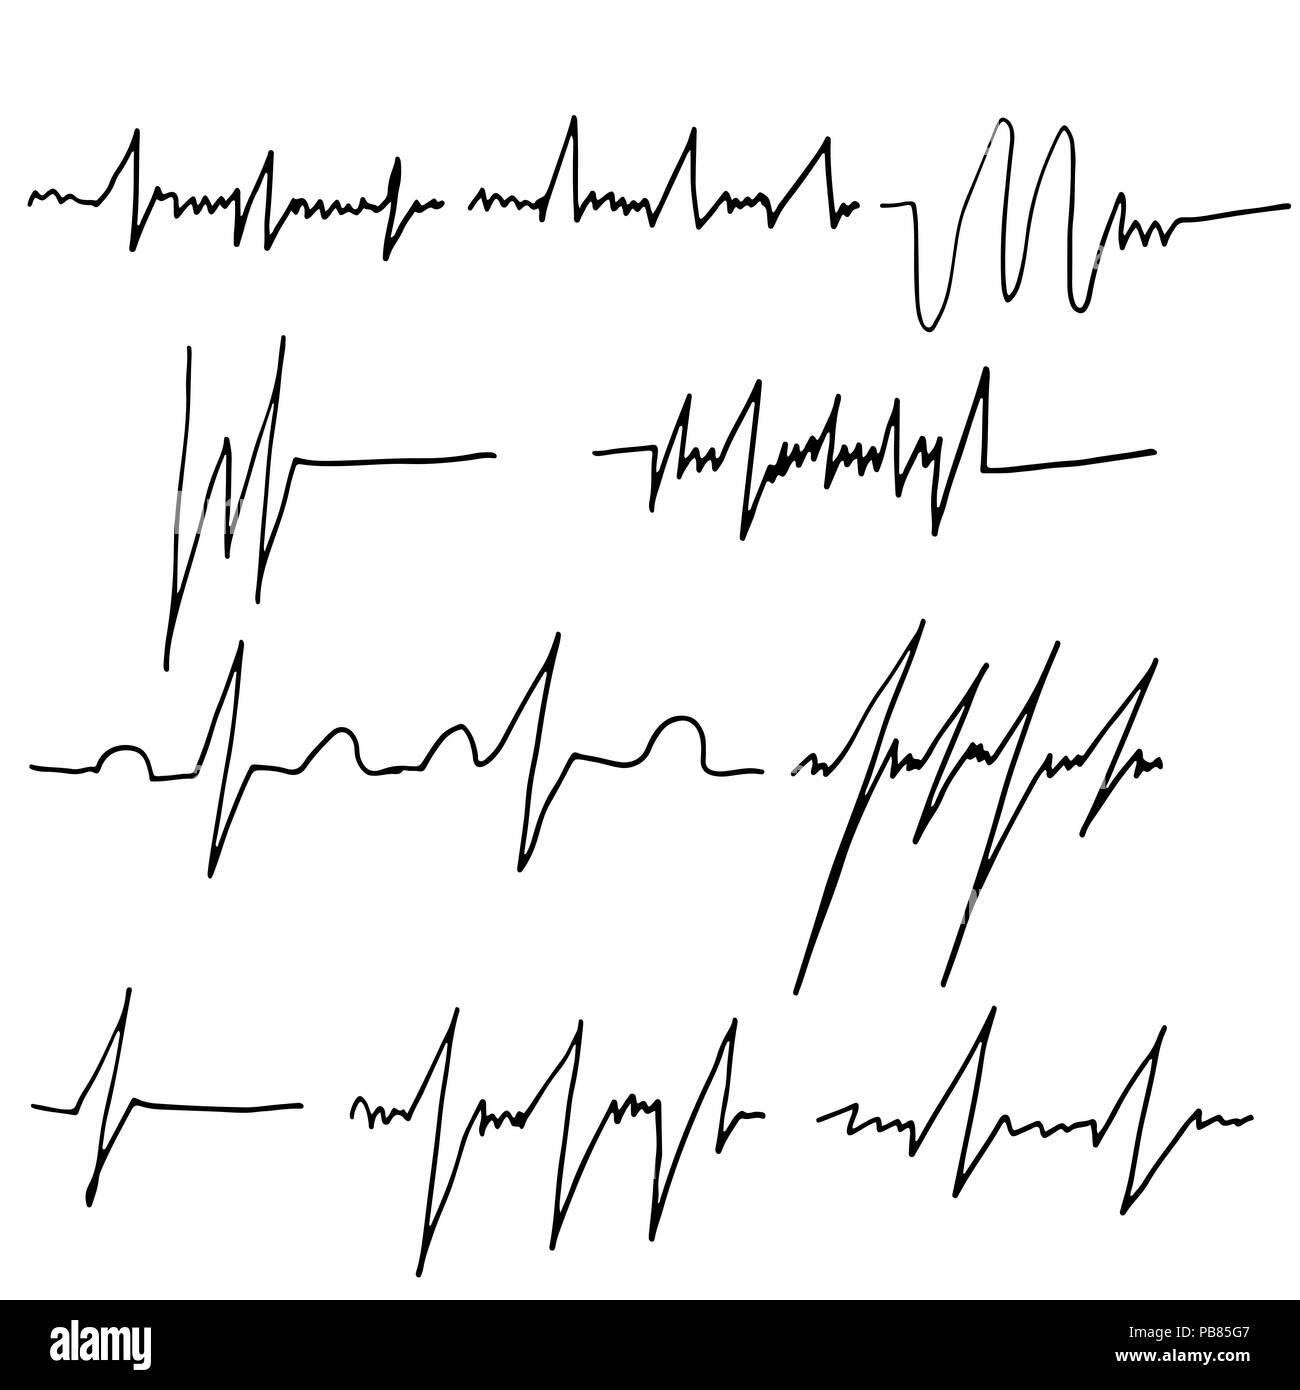

Heart rate graphics set. Cardiac systole brush. Vector illustration. Stock Vectorhttps://www.alamy.com/image-license-details/?v=1https://www.alamy.com/heart-rate-graphics-set-cardiac-systole-brush-vector-illustration-image213465623.html

Heart rate graphics set. Cardiac systole brush. Vector illustration. Stock Vectorhttps://www.alamy.com/image-license-details/?v=1https://www.alamy.com/heart-rate-graphics-set-cardiac-systole-brush-vector-illustration-image213465623.htmlRFPB85G7–Heart rate graphics set. Cardiac systole brush. Vector illustration.